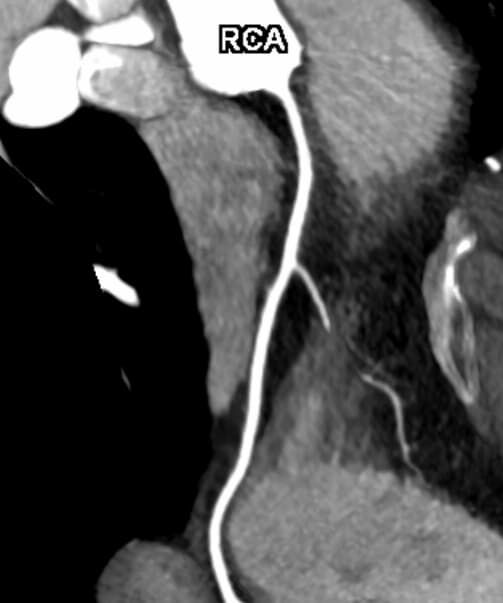

• Darstellung der Blutgefäße (sog. CT- Angiographie)

Herz

• mehrdimensionale Darstellung vasculärer Strukturen mit zahlreichen Auswertungstools